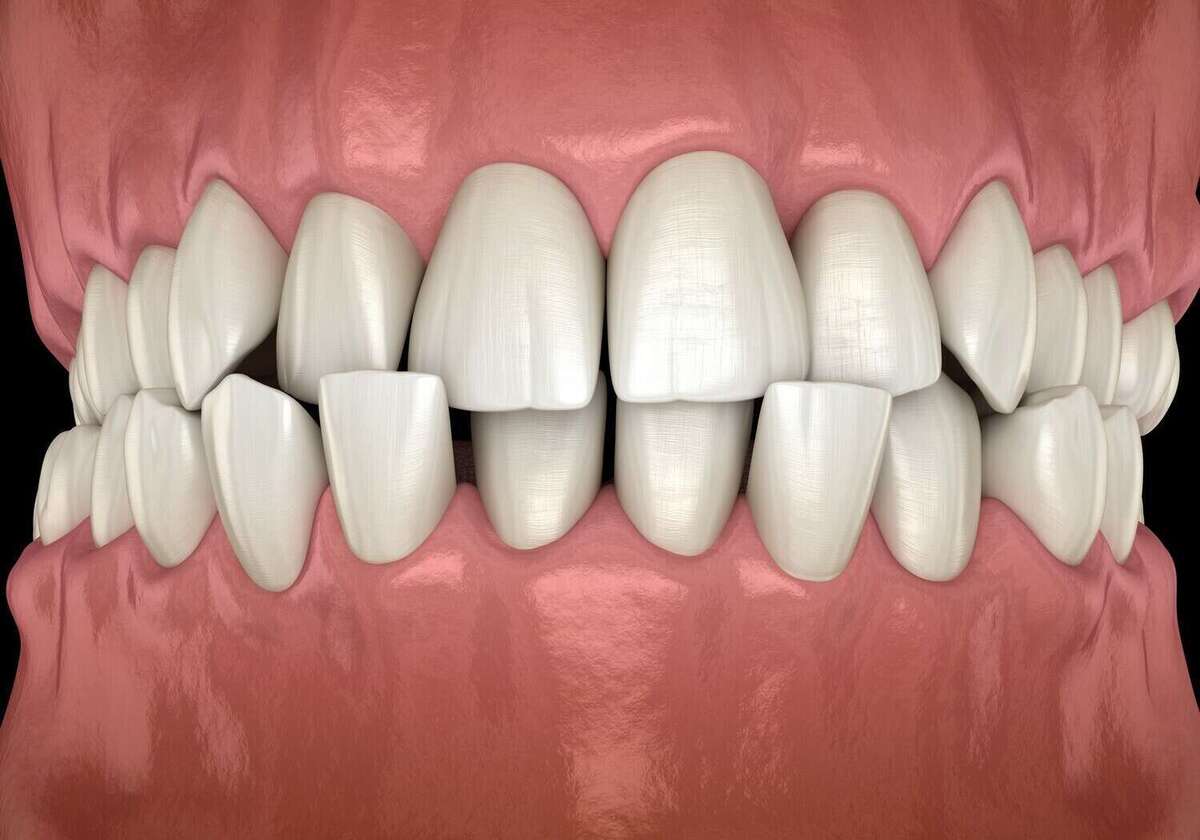

Les malpositions dentaires

Les dents se placent alors comme elles le peuvent, avec un risque de chevauchement, d’écartement excessif, de béance entre les deux arcades.

Certaines dents seront trop en avant ou trop en arrière. L’éruption de l’une sera gênée par la présence d’une autre.

Un recouvrement partiel de deux dents pourra se former, ...